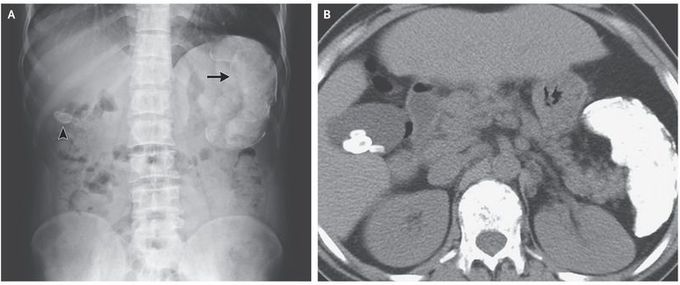

A 35-year-old man presented to the gastroenterology clinic for treatment of chronic hepatitis C virus (HCV) infection. He had a type of sickle cell disease, hemoglobin Sβ thalassemia, with recurrent, episodic abdominal pain that had been present since childhood. A complete blood count showed microcytic anemia. The total bilirubin level was 8.5 mg per deciliter (145 μmol per liter; reference range, 0.3 to 1.2 mg per deciliter [5.1 to 20.5 μmol per liter]) and the indirect bilirubin level was 6.2 mg per deciliter (106 μmol per liter; reference range, 0.1 to 1.0 mg per deciliter [1.7 to 17.1 μmol per liter]). A peripheral-blood smear showed microcytic and hypochromic red cells, target cells, nucleated red cells, and sickle cells. An abdominal radiograph, which was obtained during a previous presentation for abdominal pain, showed a radiopaque gallstone (Panel A, arrowhead) and a calcified spleen (Panel A, arrow). A computed tomographic scan of the abdomen, obtained without the administration of contrast material, showed multiple gallstones and a calcified splenic pulp and capsule (Panel B). Pigment gallstones may occur as a result of hemolysis. Bilirubin stones, which are normally radiolucent, can be radiopaque when bilirubin binds with calcium. This patient completed treatment for chronic HCV infection, and he was vaccinated against encapsulated organisms. He has continued to do well on follow-up visits.